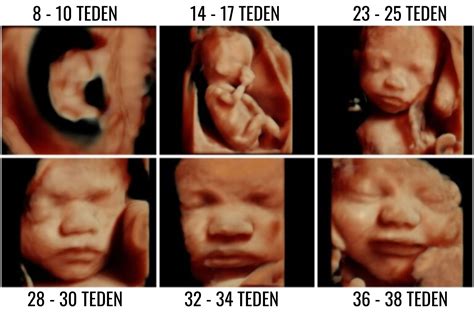

V tem obdobju se pričnejo razvijati tudi prstni odtisi, jezik in glasilke. Dojenček prične vaditi dihanje in požiranje plodovnice. Okoli 20. tedna nosečnosti, ko se opravi podroben ultrazvočni pregled, imenovan morfologija, je mogoče že opaziti spol otroka. Na morfologiji ginekolog pregleda razvoj posteljice in otroka ter oceni, ali obstajajo morebitni zapleti. V tem času mnoge nosečnice prvič občutijo nežne gibe svojega dojenčka, ki jih pogosto primerjajo s prhutanjem metuljevih kril. Ti gibi postajajo z nadaljevanjem nosečnosti vse bolj izraziti.

V 14. tednu nosečnosti plod meri 8,3 cm in tehta do 43 g. Začnejo mu rasti lasje, obrvi in trepalnice, celotno telo pa pokrijejo nežni, tanki lasje - lanugo. Tveganje za spontani splav se zniža za 75 %, nosečnica pa običajno čuti naval energije in povečan apetit. Maternica sega že nad sramno kost. V 15. tednu plod meri 12,7 cm in tehta 57 g. Na ultrazvoku lahko vidimo, da sesa palec, lahko zazna močno svetlobo od zunaj, stisne pest in se refleksno smeji. Nosečniški trebušček je že lepo viden, povprečna pridobitev teže do tega tedna je 2,3 kg. Srce prečrpa za 20 % več krvi kot izven nosečnosti. V 16. tednu plod meri 13,5 cm in tehta 70 g. Vse mišice in kosti ploda so formirane, izločanje urina in krvni obtok že delujeta. Nosečnica lahko že začuti nežne gibe ploda, še posebej, če je posteljica na zadnji steni maternice ali če je nosečnica že rodila.

V 27. tednu nosečnosti plod meri 28 cm in tehta 450 g. V njegovi koži nastaja pigment, zaradi katerega postaja rožnate ali rdeče barve. V pljučih se razvijajo krvne žile, plod pa vse bolj razlikuje zvoke in lahko reagira na glasbo ter prepozna mamin glas. Nosečnica zaradi zadrževanja tekočine in pritiska maternice na žile pogosto dobi otekle noge. V 28. tednu plod meri 38 cm in tehta 1050 g. Rastejo mu lasje, trepalnice in obrvi postanejo debelejši, obrazne poteze bolj izrazite, plod pa pogosto zeha. Količina plodovnice je maksimalna med 28. in 32. tednom.

V 30. tednu nosečnosti plod tehta med 1200 in 1400 g. Povečuje se količina maščobnega tkiva. Prebava se še bolj upočasni, zato se priporoča prehrana bogata z vlakninami in zadostno količino tekočin. Pridobitev teže do 30. tedna naj ne bi presegla 10 kg. V 32. tednu plod tehta 1600 do 1800 g in meri 42 cm. Koža je rožnate barve in gladka, nohti so prisotni na rokah in nogah. Zaradi povečane količine krvi, hormonskih sprememb in stresa pred porodom se lahko stopnjuje hitro bitje srca.

V 36. tednu plod meri 46 cm in tehta 2700 g. Njegovo telo je še vedno pokrito s sirastim in mastnim premazom (verniksom), ki ščiti otrokovo kožo. Čas je za zadnje laboratorijske preiskave pred porodom. V kolikor je plod obrnjen z ritko navzdol, je čas za zunanji obrat. V 37. tednu je plod že donošen, dolg 48 cm in težak 2950 g. Spušča se počasi v medenico. Porod se lahko začne kadarkoli. V 38. tednu plod meri 50 cm in tehta 3100 g. Dolžina ploda se ne bo več spreminjala, rast pa je težko natančno oceniti. Količina plodovnice se zmanjšuje, zato so plodovi gibi nežni. Zatekanje nog in zadrževanje tekočine v telesu je še bolj izrazito.